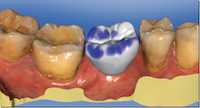

Le guide chirurgical, aussi réalisé par CFAO, ouvre la possibilité, en fonction du contexte parodontal, de réaliser une chirurgie « flapless ».

La position des implants est enregistrée à l’aide de transferts numériques et la restauration peut être réalisée soit au laboratoire de prothèse, soit au cabinet dentaire si celui-ci est équipé d’un système de CFAO directe et si la restauration est unitaire.